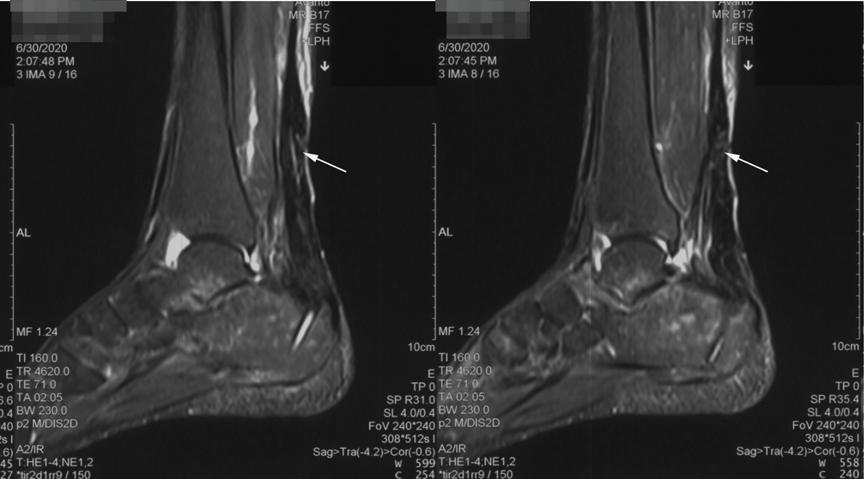

杨阿姨术后右踝关节石膏固定了2周,又戴了1个月左右的护具,恢复的很不错。由于对广场舞的热爱,重返舞场是杨阿姨最大的心愿,因此医嘱遵从性特别好。术后2个月来门诊复查时,已经基本恢复了右踝关节的正常功能。查体Thompson征阴性,踝关节活动度良好,并能轻松踮脚了。

图3、 术后2月复查MRI示跟腱愈合良好